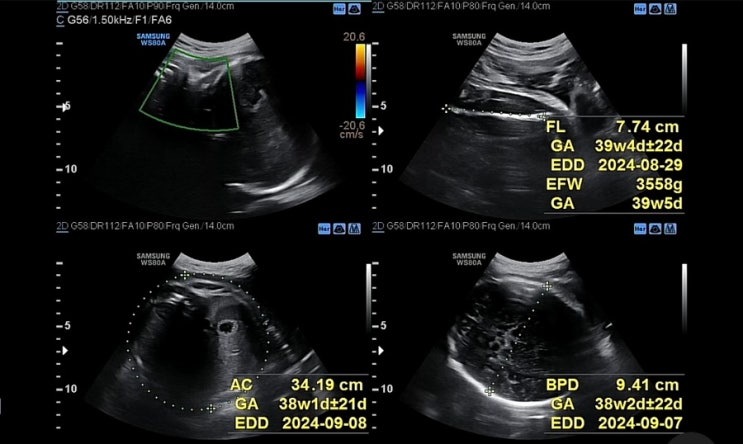

[임신 40주] 아직 안 끝났다

39주 검진일에 잡은 유도분만의 날(39주차 6일, 8/23)이 다가왔고, 긴장되는 마음으로 아침밥도 든든하게 ...